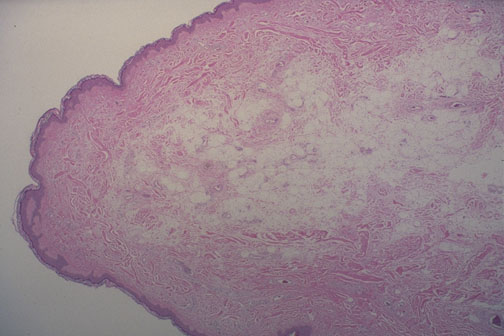

Microscopically, a skin tag has a loose connective tissue center covered by epidermis.